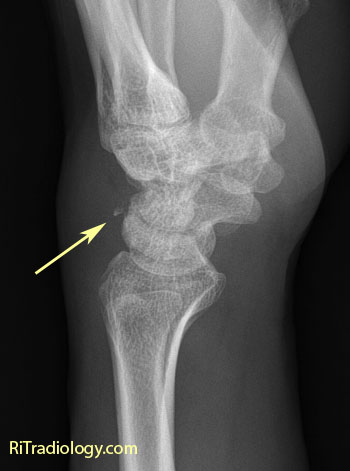

Fracture Triquetrum